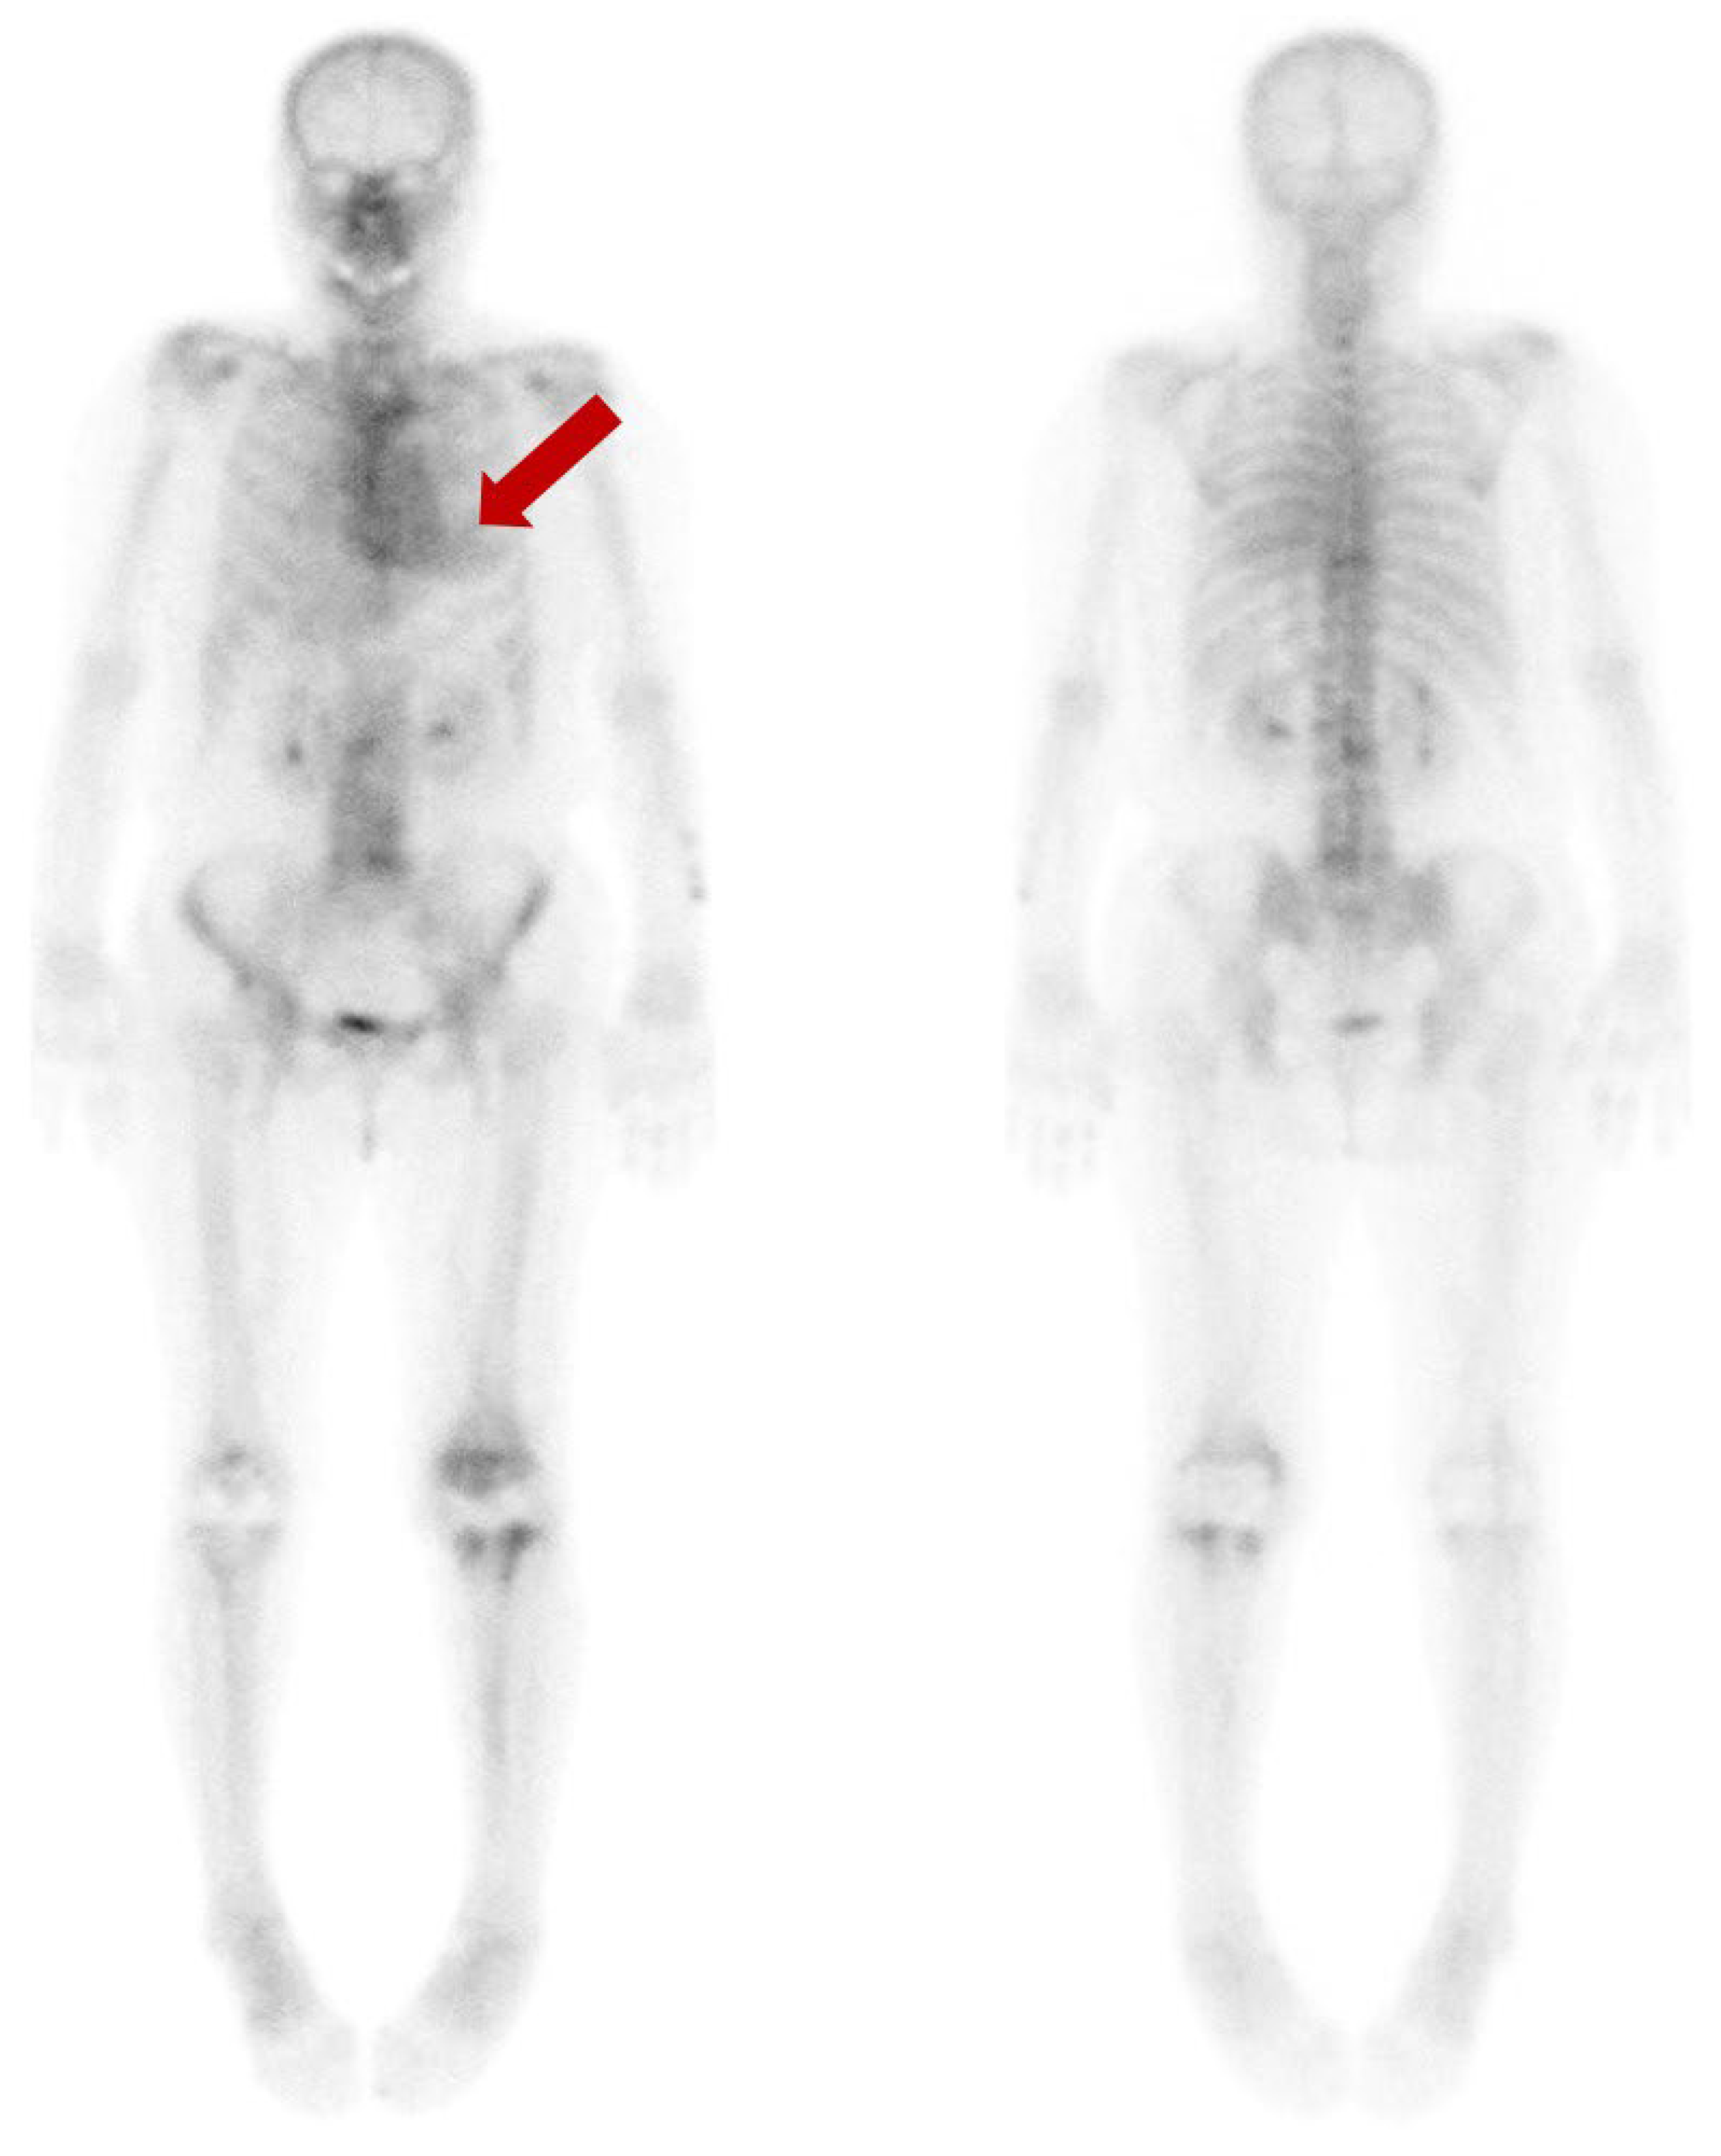

Diffuse Cardiac Uptake Misdiagnosed as Cardiac Amyloidosis in Bone Scan

Lee, Y.; Jang, J.; Na, S.J. Diffuse Cardiac Uptake Misdiagnosed as Cardiac Amyloidosis in Bone Scan. Diagnostics 2023, 13, 3342. https://doi.org/10.3390/diagnostics13213342